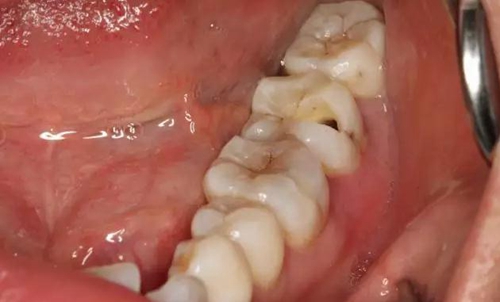

圖1.患者自述右側(cè)下后牙牙齦紅腫,咀嚼不適。術(shù)前口內(nèi)像:37頰側(cè)牙齦紅腫

10.jpg